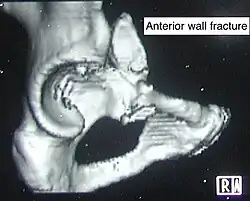

| Anterior wall | This fracture is uncommon, typically occurring when the injuring force is applied from the side, against the greater trochanter of the femur bone, as in a fall on the side or being hit on the side. | Transverse + posterior wall | These fractures are extension of elementary fractures. With involvement of posterior wall, the difficulty in treatment increases. These fractures are rarely amenable to non-surgical treatment. Due to posterior wall fracture, the hip is usually dislocated posteriorly, requiring immediate reduction of dislocation and surgical reconstruction after few days.

- Anterior wall fracture: Iliac oblique view

Anterior wall fracture

Anterior wall fracture -

As seen on 3D CT image

As seen on 3D CT image -